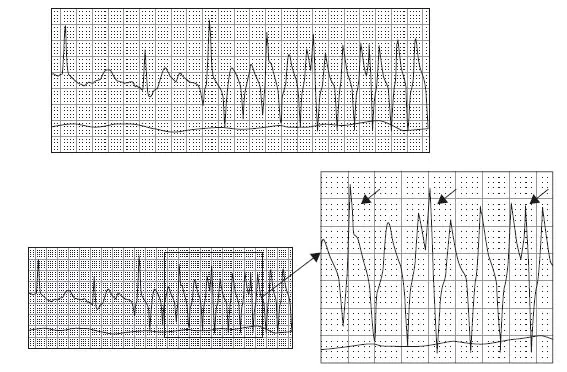

2. Atrial fibrillation, ventricular rate 96, artifact. The rhythm is initially irregularly irregular without distinct atrial activity, consistent with atrial fibrillation. The rhythm terminates with an episode of markedly irregular and rapid QRS complexes with changing morphologies. Considerations with this type of rhythm should include atrial fibrillation with Wolff-Parkinson-White syndrome (WPW), torsades de pointes, or artifact. The presence of “sharp points” at both the apices and nadirs of the QRS complexes is more consistent with artifact. See figure below.

This figure corresponds to case #2. Atrial fibrillation with subsequent wide QRS complex tachycardia

Note the arrows indicating QRS complexes which are occurring through this artifactual wide QRS complex event. The clinical correlation in this setting also aids in the interpretation—noting that the patient remains unchanged with a pulse corresponding to the original rhythm is helpful as well as observing rigors in this setting.